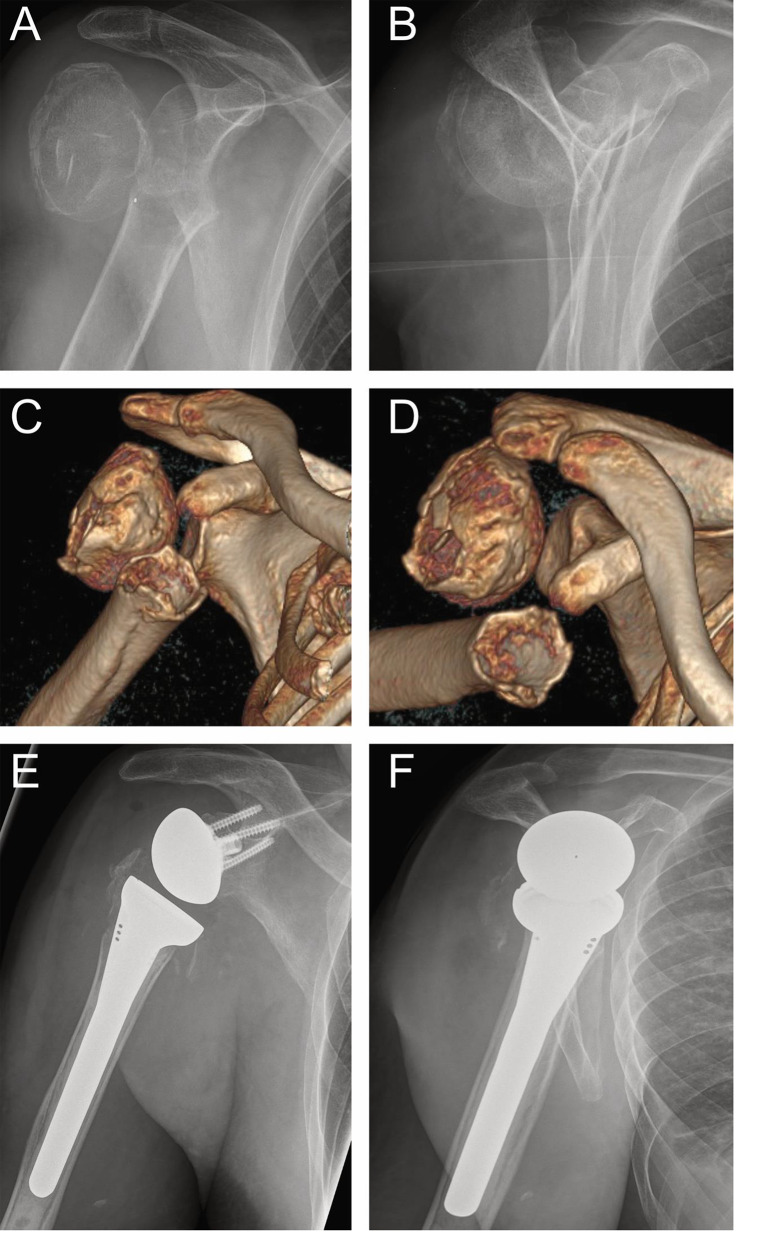

The Section for Skeletal Trauma and Sports Injuries of the European Society for Trauma and Emergency Surgery (ESTES) has reached a consensus among European countries in the treatment of proximal humerus fractures in a working group. As a result the ESTES recommendations on proximal humerus fractures in the elderly were published in 2021. The various treatment options and algorithms for this are now described in more detail and the procedures were explained in several related specialist articles. The recommendations include conservative and four possible surgical treatment options (ORIF, nailing, hemi- and total inverse arthroplasty). This article deals with hemi- and total inverse arthroplasty. Reverse total shoulder arthroplasty (RTSA) has emerged as a key treatment for complex proximal humerus fractures in elderly patients. It offers significant advantages in restoring function, alleviating pain, and providing durable outcomes compared to alternative approaches. Despite challenges related to implant complications and surgical expertise, ongoing advancements in technology and techniques continue to improve its effectiveness. With the rising incidence of complex fractures, RTSA is expected to play an increasingly vital role in maintaining the quality of life in aging populations.